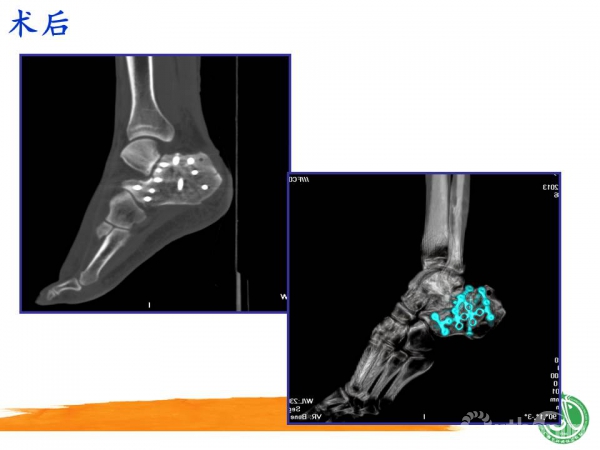

2015-01-12 文章来源:广州军区武汉总医院骨科 魏世隽 我要说